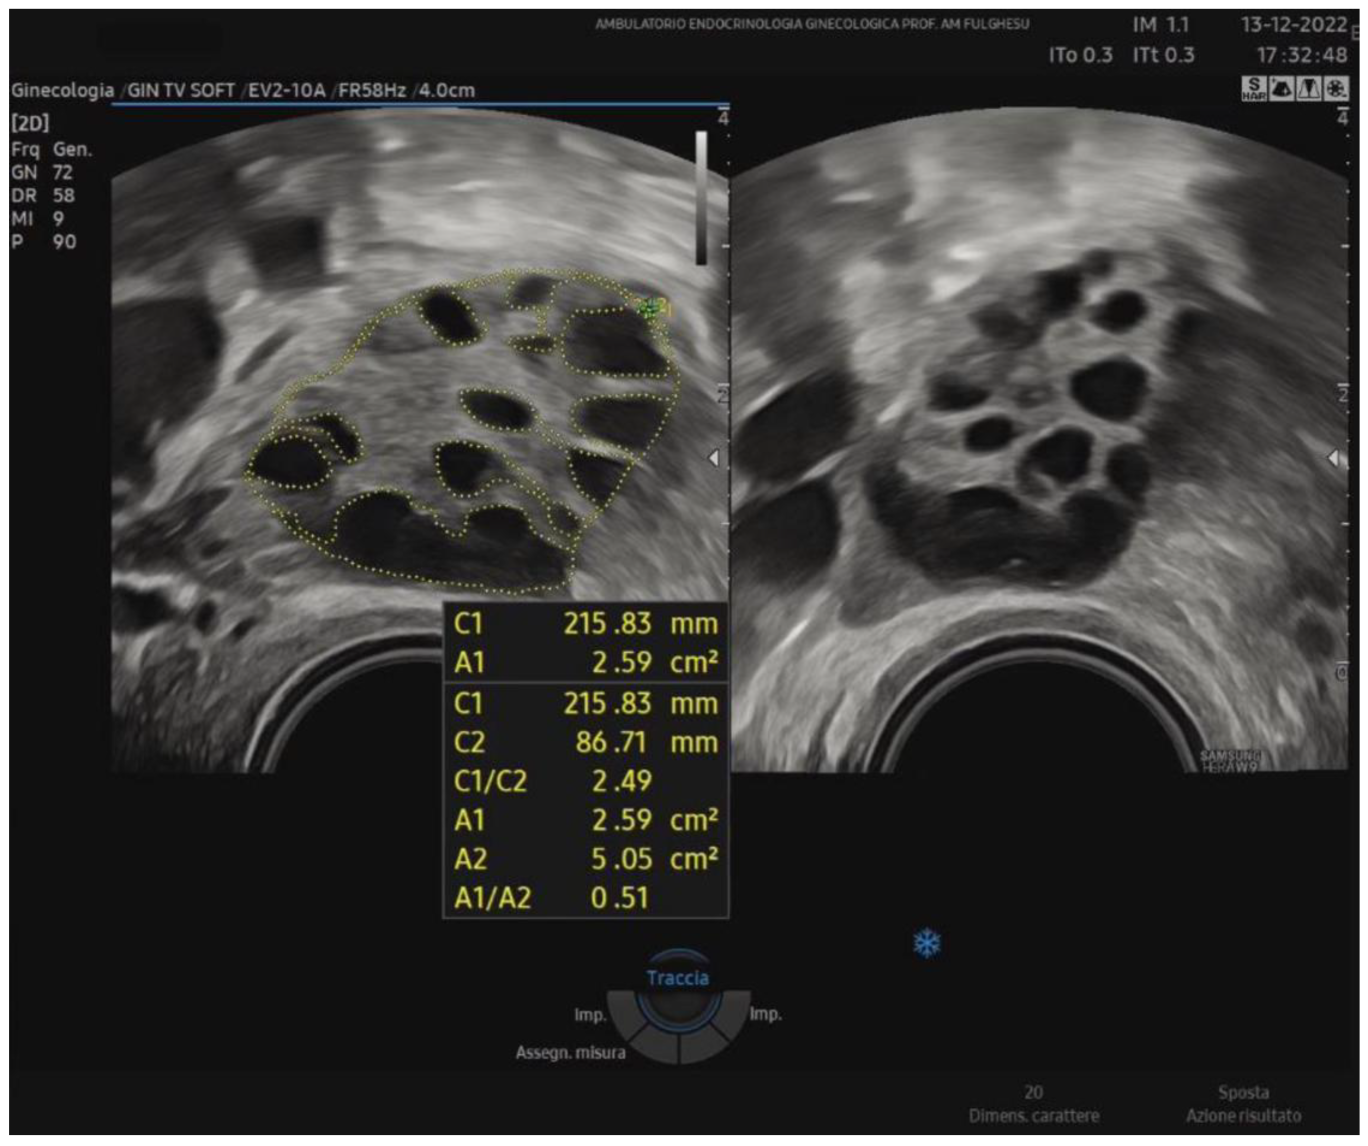

Recent investigations focus on new ultrasound markers to better characterize ovarian morphology. One method is the stromal area/ovarian area (SA/OA) ratio, which, with a cut-off of 0.32, has been proposed as a significant predictor of elevated androstenedione and testosterone levels [40]. Because the Rotterdam criteria are not recommended for adolescents due to transabdominal scans and the high prevalence of PCOM in healthy teens, some authors have suggested measuring the SA/OA ratio to reduce the risk of overdiagnosis. In studies involving normocyclic and non-hyperandrogenic adolescent girls, applying the Rotterdam guidelines (follicle count ≥ 12, OV > 10 mL) and setting the standard SA/OA ratio to ≤0.3 led to the classification of ovaries into three groups: normal morphology (NOM), PCOM with normal SA/OA (PCOM-NS), and PCOM with increased SA/OA (PCOS-IS). Notably, the prevalence of PCOM-IS remained constant across different post-menarche ages, indicating that an increased stromal ratio might be a more stable feature associated with androgen excess. Indeed, PCOM may be considered a normal and transient physiological phase in ovarian development during early adolescence, predominantly observed in the first 1–3 years post-menarche because of an immature hypothalamic-pituitary axis [41,42]. Around 1985, Adams et al. noted the characteristic peripheral arrangement of follicles around a core of hyperechoic stroma [34]. Similarly, Dewailly in 1994 observed that ovarian hypertrophy, indirectly linked to stromal hypertrophy, was easy to measure and correlated with PCOS [43]. In recent decades, numerous attempts have been made to quantify stromal echogenicity and thickness more objectively. For instance, stromal and myometrial echogenicity have been compared, considering that normal stromal echogenicity should be slightly lower than the myometrium. However, operator subjectivity and equipment differences have hindered standardization. In 2001, Fulghesu et al. [44] proposed quantifying the stromal percentage in the central zone using calipers to outline the ovarian periphery and the stromal core on a still ultrasound image corresponding to the maximum planar section of the ovary (SA/OA ratio) (Figure 1).

Figure 1.

Example of the SA/OA ratio calculation on a median ovarian section with outlined ovarian and stroma areas during a TV-US scan. A1: total stromal area; A2: ovarian area; A1/A2: SA/OA ratio (>0.32).

With this type of measurement, values of SA/OA > 0.32, which reflect a stroma occupying more than one-third of the ovary in the midsection, suggest a more pronounced androgenic profile, corresponding to a higher likelihood of PCOS. The stromal area-to-total ovary area ratio can be assessed without the need for other technologies using standard ultrasound and eliminates the problems of subjective stromal assessment encountered previously. Belosi et al. [45] confirmed that the SA/OA ratio shows minimal inter-operator variability, high diagnostic accuracy, and a strong correlation with plasma androgen levels. Moreover, by adding SA/OA ratio measurement, one can identify subgroups of patients with borderline or NIH-negative status who nonetheless display underlying hyperandrogenism. In 2007, a multicenter study in Italy corroborated these findings, demonstrating that the SA/OA ratio best predicts elevated androstenedione and testosterone levels among the various ultrasound parameters [40]. In conclusion, ultrasound-based diagnosis of PCOS still relies on the Rotterdam criteria (2003). However, adding a stromal evaluation (SA/OA ratio) may significantly improve the identification of hyperandrogenic phenotypes. Quantifying both stromal area and follicle distribution is crucial to accurately diagnosing PCOS, offering the possibility of distinguishing different phenotypes and optimizing patient management.